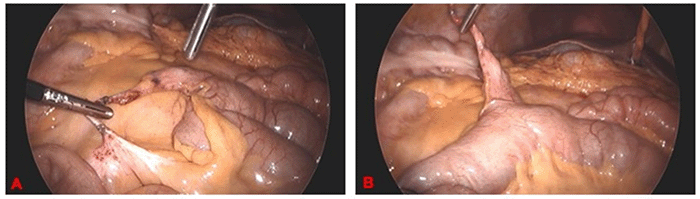

The patient, a 51-year-old female with a history of cleft palate and arcuate uterus and no previous abdominal surgeries, presented to the ED with sudden abdominal pain. The pain, which started five hours before the ED visit, was constant and maximal. She denied any prior history of similar episodes. She ate breakfast prior to the onset of pain but experienced intolerance to oral intake since and began dry heaving several hours prior to presentation. The patient did not endorse bowel irregularities. Physical examination revealed right lower quadrant guarding and widespread abdominal tenderness. Lab results, except for a lactate level of 2.7, were normal. A contrast-enhanced CT scan displayed mildly dilated distal small bowel loops with a focal transition point in the right lower quadrant, consistent with acute-on-chronic small bowel obstruction and a normal appendix (Figure 1).

Figure 1. Abdominpelvic CT Images. Published with Permission

Loops of mildly dilated distal small bowel with focal transition point in the right lower quadrant (denoted by arrows), in coronal (A) and axial (B) planes, consistent with acute-on-chronic small bowel obstruction